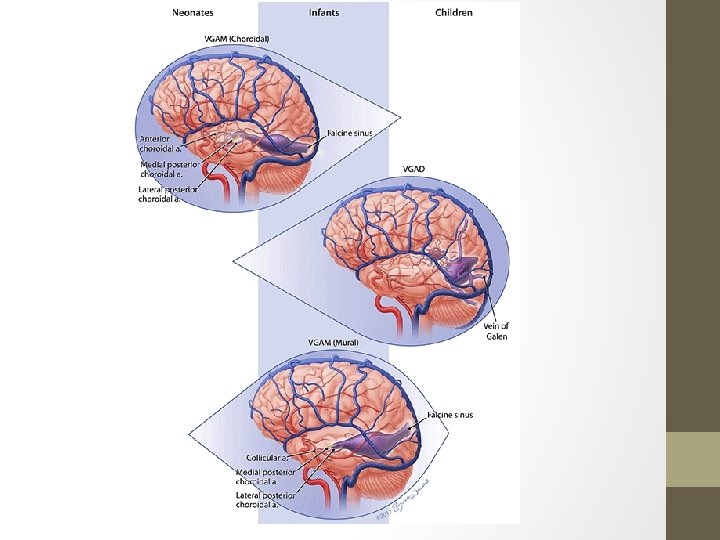

• Presentation commonly with high output cardiac failure in neonates while mostly hydrocephalus in infants and children • Angiography: gold std • Classification - Lasjaunias classification: Ø Choroidal: tend to present earlier (neonate) with more severe shunts&high output cardiac failure Ø Mural: present later (infant) and typically with hydrocephalus. Fewer fistulas-high outflow restriction -Yasargil Classification Ø type I: small pure cisternal fistula between the vein of Galen and either the pericallosal arteries (anterior or posterior) or posterior cerebral artery Ø type II: multiple fistulous communications between the vein of Galen and the thalamoperforating vessels Ø type III: high flow mixed type I and II Ø type IV: parenchymal arteriovenous malformation (AVM) with drainage into the vein of Galen

Tx&Prognosis • Arterial feeder and fistula occlusion • Transtorcular or transvenous embolisation of the dilated vein • Prognosis is largely determined by the presence or absence of cardiac failure. Thus choroidal types and those presenting in the neonatal period do poorly.